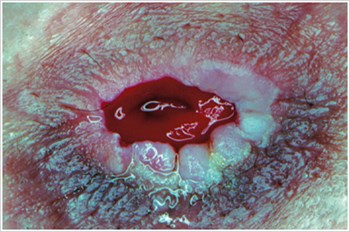

Pioderma gangrenoso

Descripción/Causas:

Enfermedad inflamatoria de la piel que se observa a menudo en pacientes con enfermedad inflamatoria intestinal (EII), como la enfermedad de Crohn o la colitis ulcerosa.

Síntomas:

- Úlceras infectadas, rojas, dolorosas, de forma irregular con márgenes enrollados de color rojo a púrpura; Aparecen en piernas, glúteos, cara y zona periestomal.